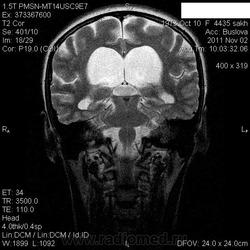

Образование III желудочка?

Прошу помощи!Вернее, мой коллега.Мужчина с подозрением на стволовой инсульт с жалобами на головокружение.Ствол показался интактным, а выявилось  непонятное образование  III желудочка+ окклюзионная (?)гидроцефалия . Хочется услышать ваши мнения-не совсем понятно, еслли честно))))

может просто гиперпульсация ликвора? Сильвиев зияет,  структуры ЗЧЯ тоже атрофичны...

у меня недавно была пациентка с похожей картинкой (исключая ЗЧЯ). В другом центре заподозрили образование третьего желудочка (снимки были отвратного качества, я на них не нашёл никаких признаков). Рекомендовали, правда ненастойчиво, контраст. пациентка пришла к нейрохирургу, тот её направил в наш центр на исследование с контрастом. даже без контраста и на обычных 5-тимиллиметровых срезах были видны спаечные изменения в водопроводе. поставил миллиметровые сагиттальные срезы, на которых стали отчётливо видны 2 спайки. сделали таки контраст, чтобы её в третий раз не отправили на МРТ, на котором никаких об'ёмных образований конечно же не было.

Если это намек на окклюзионную гидроцефалию на уровне водопровода, то почему такое состояние ЗЧЯ и почему так расширен сильвиев водопровод? Может все же гиперпродукция ликвора (анамнез надо уточнить, может какие менингиты, ЧМТ, САК были?)...

я не намекал, упаси Бог, здесь я окклюзии водопровода не вижу. просто о похожести картинки говорю. в моём случае и расширения четвёртого желудочка не было. здесь или спайка где-то совсем низко (ниже большой цистерны) или гиперпродукция ликвора....

И у меня недавно было то же - поставил внутреннюю гидроцефалию без нарушения ликворооттока.

В данном случае, на мой взгляд - дифряда особо никакого, причины окклюзии не видно, поэтому следует предположение о внутренней гидроцефалиии за счет гипепродукции ликвора...